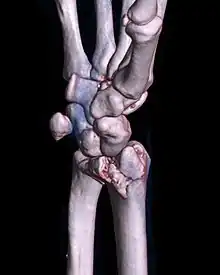

A palmar Barton's fracture of the right wrist, as shown on a 3D-rendered CT scan

A Barton's fracture is a type of wrist injury where there is a broken bone associated with a dislocated bone in the wrist, typically occurring after falling on top of a bent wrist.[1] It is an intra-articular fracture of the distal radius with dislocation of the radiocarpal joint.[2]